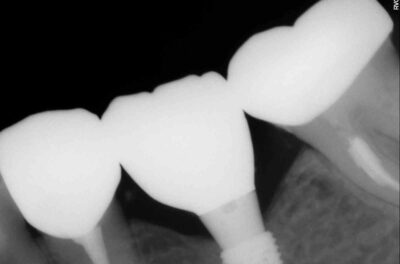

Протезирование коронками из диоксида циркония, после эндодонтического лечения — Исламов Л.А.(01.04.2026)